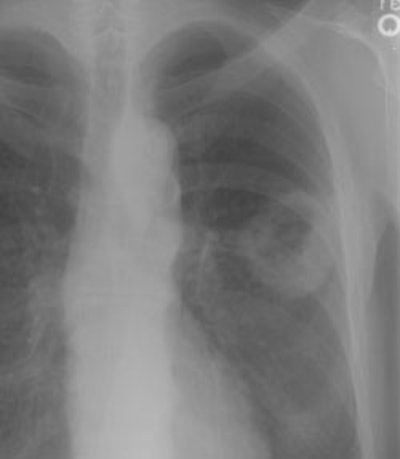

Example 2: False-negative CT exam -- this patient had an adenocarcinoma in the right upper lobe that measured less than 3 cm in size (T1 lesion). The ipsilateral mediastinal nodes identified by staging CT were not pathologic by size criteria. The surgical team elected to proceed to thoracotomy without mediastinoscopy. At surgery, the small right paratracheal nodes which measured less than 1 cm where found to contain microscopic foci of tumor (N2 nodes). The patient was staged histopathologically as T1N2M0 (Stage IIIA).

NOTE: Click image to enlarge